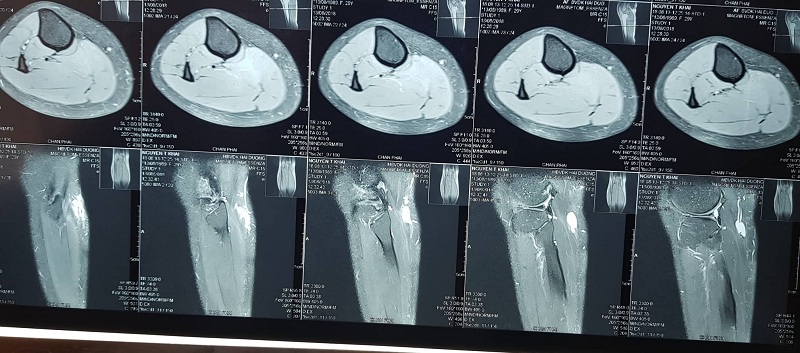

- Bệnh nhân thứ 2: U cuộn mạch cẳng chân

Cận lâm sàng: Có 2 phương pháp cận lâm sàng chính có thể được sử dụng để xác định chẩn đoán u cuộn mạch, đó là siêu âm và chụp MRI.

Cộng hưởng từ(MRI): có ưu điểm là trong trường hợp phát hiện ra thì sẽ đánh giá được chính xác khối u.